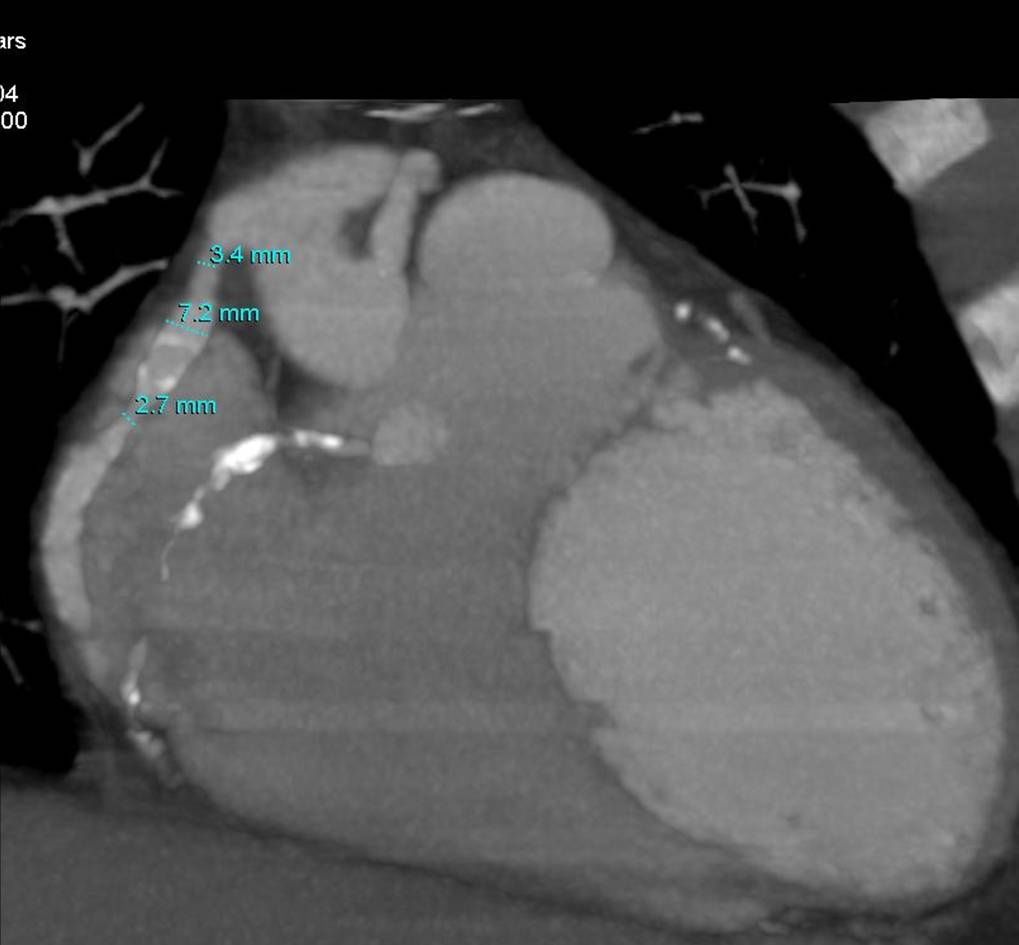

The non-invasive imaging modality of multi-detector computed tomography has dramatically evolved the last ten years and that is due to hardware and software developments. The newer generation of scanners allows increased spatial and temporal resolution that improves the clinical reliability giving further insights into the evaluation of coronary artery disease. Heart morphology imaging followed by studies of myocardial function and assessment of cardiac valves can be performed from the information derived from the data of the coronary artery examination. Also, the venous anatomy of the heart, coronary artery bypass grafts, stents, and cardiac tumors can be imaged and evaluated when necessary. For the beneficial use of this method, entrance criteria for different patient groups need to be set in order to allow improved outcome of multi-detector CT.